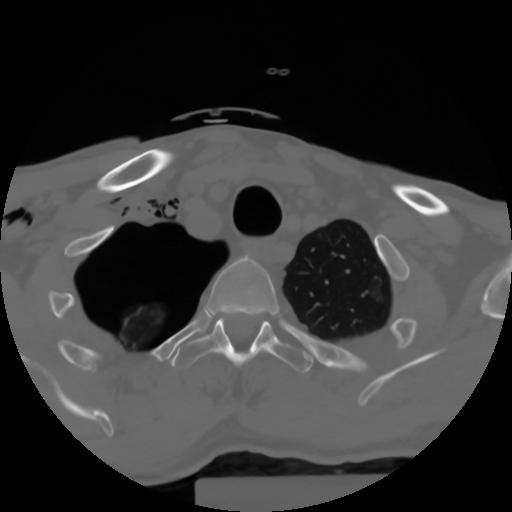

10 P.BLANDAS,,Axial,2.0,P.BLANDAS,,